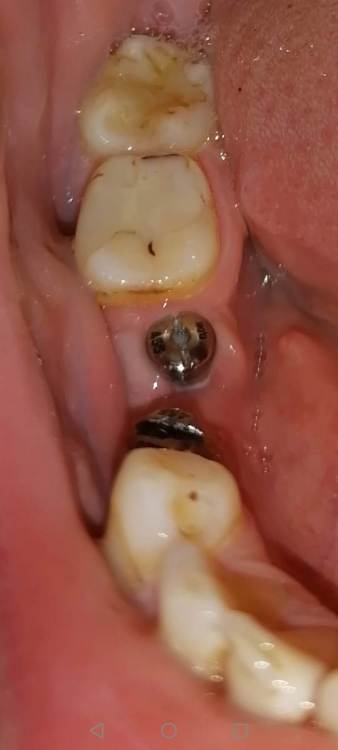

Sergey5263883 Опубликовано 23 января, 2022 Поделиться Опубликовано 23 января, 2022 (изменено) Добрый день! Уважаемые доктора подскажите пожалуйста, 2,5 месяца назад поставили импланты megagen . Спустя 2 месяца поставили формирователи. За все это время никаких болей, жалоб и тд у меня не было. Вчера случайно обратил внимание, что формирователь на 6-ке с одной стороны как бы оголен, или не утоплен. Скажите пожалуйста это нормально? Очень переживаю Снимок к сожалению есть только до установки Формирователя Изменено 23 января, 2022 пользователем Sergey5263883 Ссылка на комментарий

Irouil Опубликовано 23 января, 2022 Поделиться Опубликовано 23 января, 2022 Вокруг формирователей тоже надо поддерживать достойный уровень гигиены в остальном все выглядит нормально 1 Ссылка на комментарий

red_butler Опубликовано 23 января, 2022 Поделиться Опубликовано 23 января, 2022 сделайте снимок с формирователями 1 Ссылка на комментарий